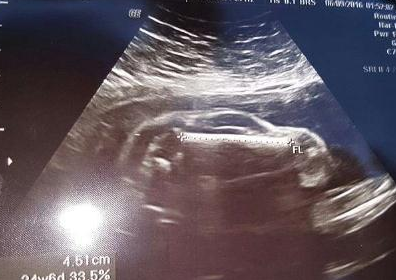

怀孕7个月的准妈妈去做超音波检查,发现宝宝伸出了两根手指。

948996dd652dcc69ccadd93838cc9b1c.png